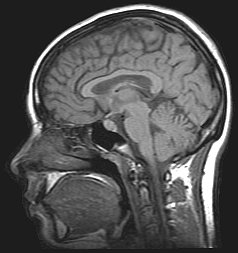

Ressonância magnética craniana

Ressonância magnética de um paciente com coriocarcinoma. A hipertensão intracraniana severa causou uma grave hernia cerebral.